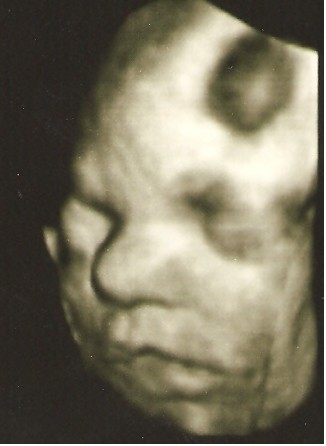

Byłam z Mamą i Mężem i wszyscy troje mieliśmy łezki w oczach jak zobaczyliśmy Młodą na 4D:)

pozdrawiamy :) z uśmiechem Jasi: ---> uśmiech Jasi

Mąż twierdzi, , że Jasia na ostatniej fotce, złości się identycznie jak ja ;)